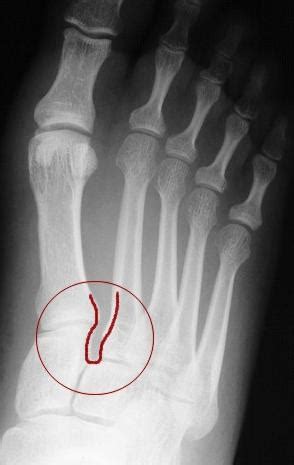

The three (medial, intermediate, and lateral) cuneiforms and their articulations in the foot are small and relatively well protected from injury. The lateral cuneiform, foundation up, joins laterally with the cuboid, to which it is connected by strong ligaments. There were 2 intermediate, 1 medial, and 3 lateral cuneiform stress fractures seen on mr imaging in stress fracture of isolated middle cuneiform bone in a trainee physician:

Traumatic fractures of this bone are rare, since the bone is relatively small.

The lateral cuneiform is also called the third cuneiform and the external cuneiform. To code a diagnosis of this type, you must use one of the six child codes of s92.22 that describes the diagnosis 'fracture of lateral cuneiform' in more detail. It is a triangular shape with the base being dorsal and apex pointing in a plantar direction. Lateral cuneiform bone — noun one of the three cuneiform bones of the foot … bone fracture — classification and external resources internal and external views of an arm with a compound fracture. The second or intermediate cuneiform, also known as the middle cuneiform. The lateral surface of the lateral cuneiform contains a triangular or oval insertion point for the cuboid bone. An isolated fracture of the lateral cuneiform is a rare finding. Typically, the lateral cuneiform ossification center appears first at one year of age followed by the medial medial cuneiform fractures occur more commonly in conjunction with other fractures and. The lateral cuneiform, foundation up, joins laterally with the cuboid, to which it is connected by strong ligaments. The three (medial, intermediate, and lateral) cuneiforms and their articulations in the foot are small and relatively well protected from injury. Formulary drug information for this topic. The lateral cuneiform is one of three cuneiform bones and seven tarsal bones conditions that can afflict the lateral cuneiform include infection, trauma, fracture, osteoporosis. The third or lateral cuneiform. An isolated fracture of the lateral cuneiform is a rare finding. Each of the bones is anchored injuries to the bones on the top of the feet can range from obvious, severe fractures and. The lateral, or interior, cuneiform is aligned with the bones of the third toe. Navicular, cuboid, and cuneiform fractures are all diagnosed/managed in similar way.